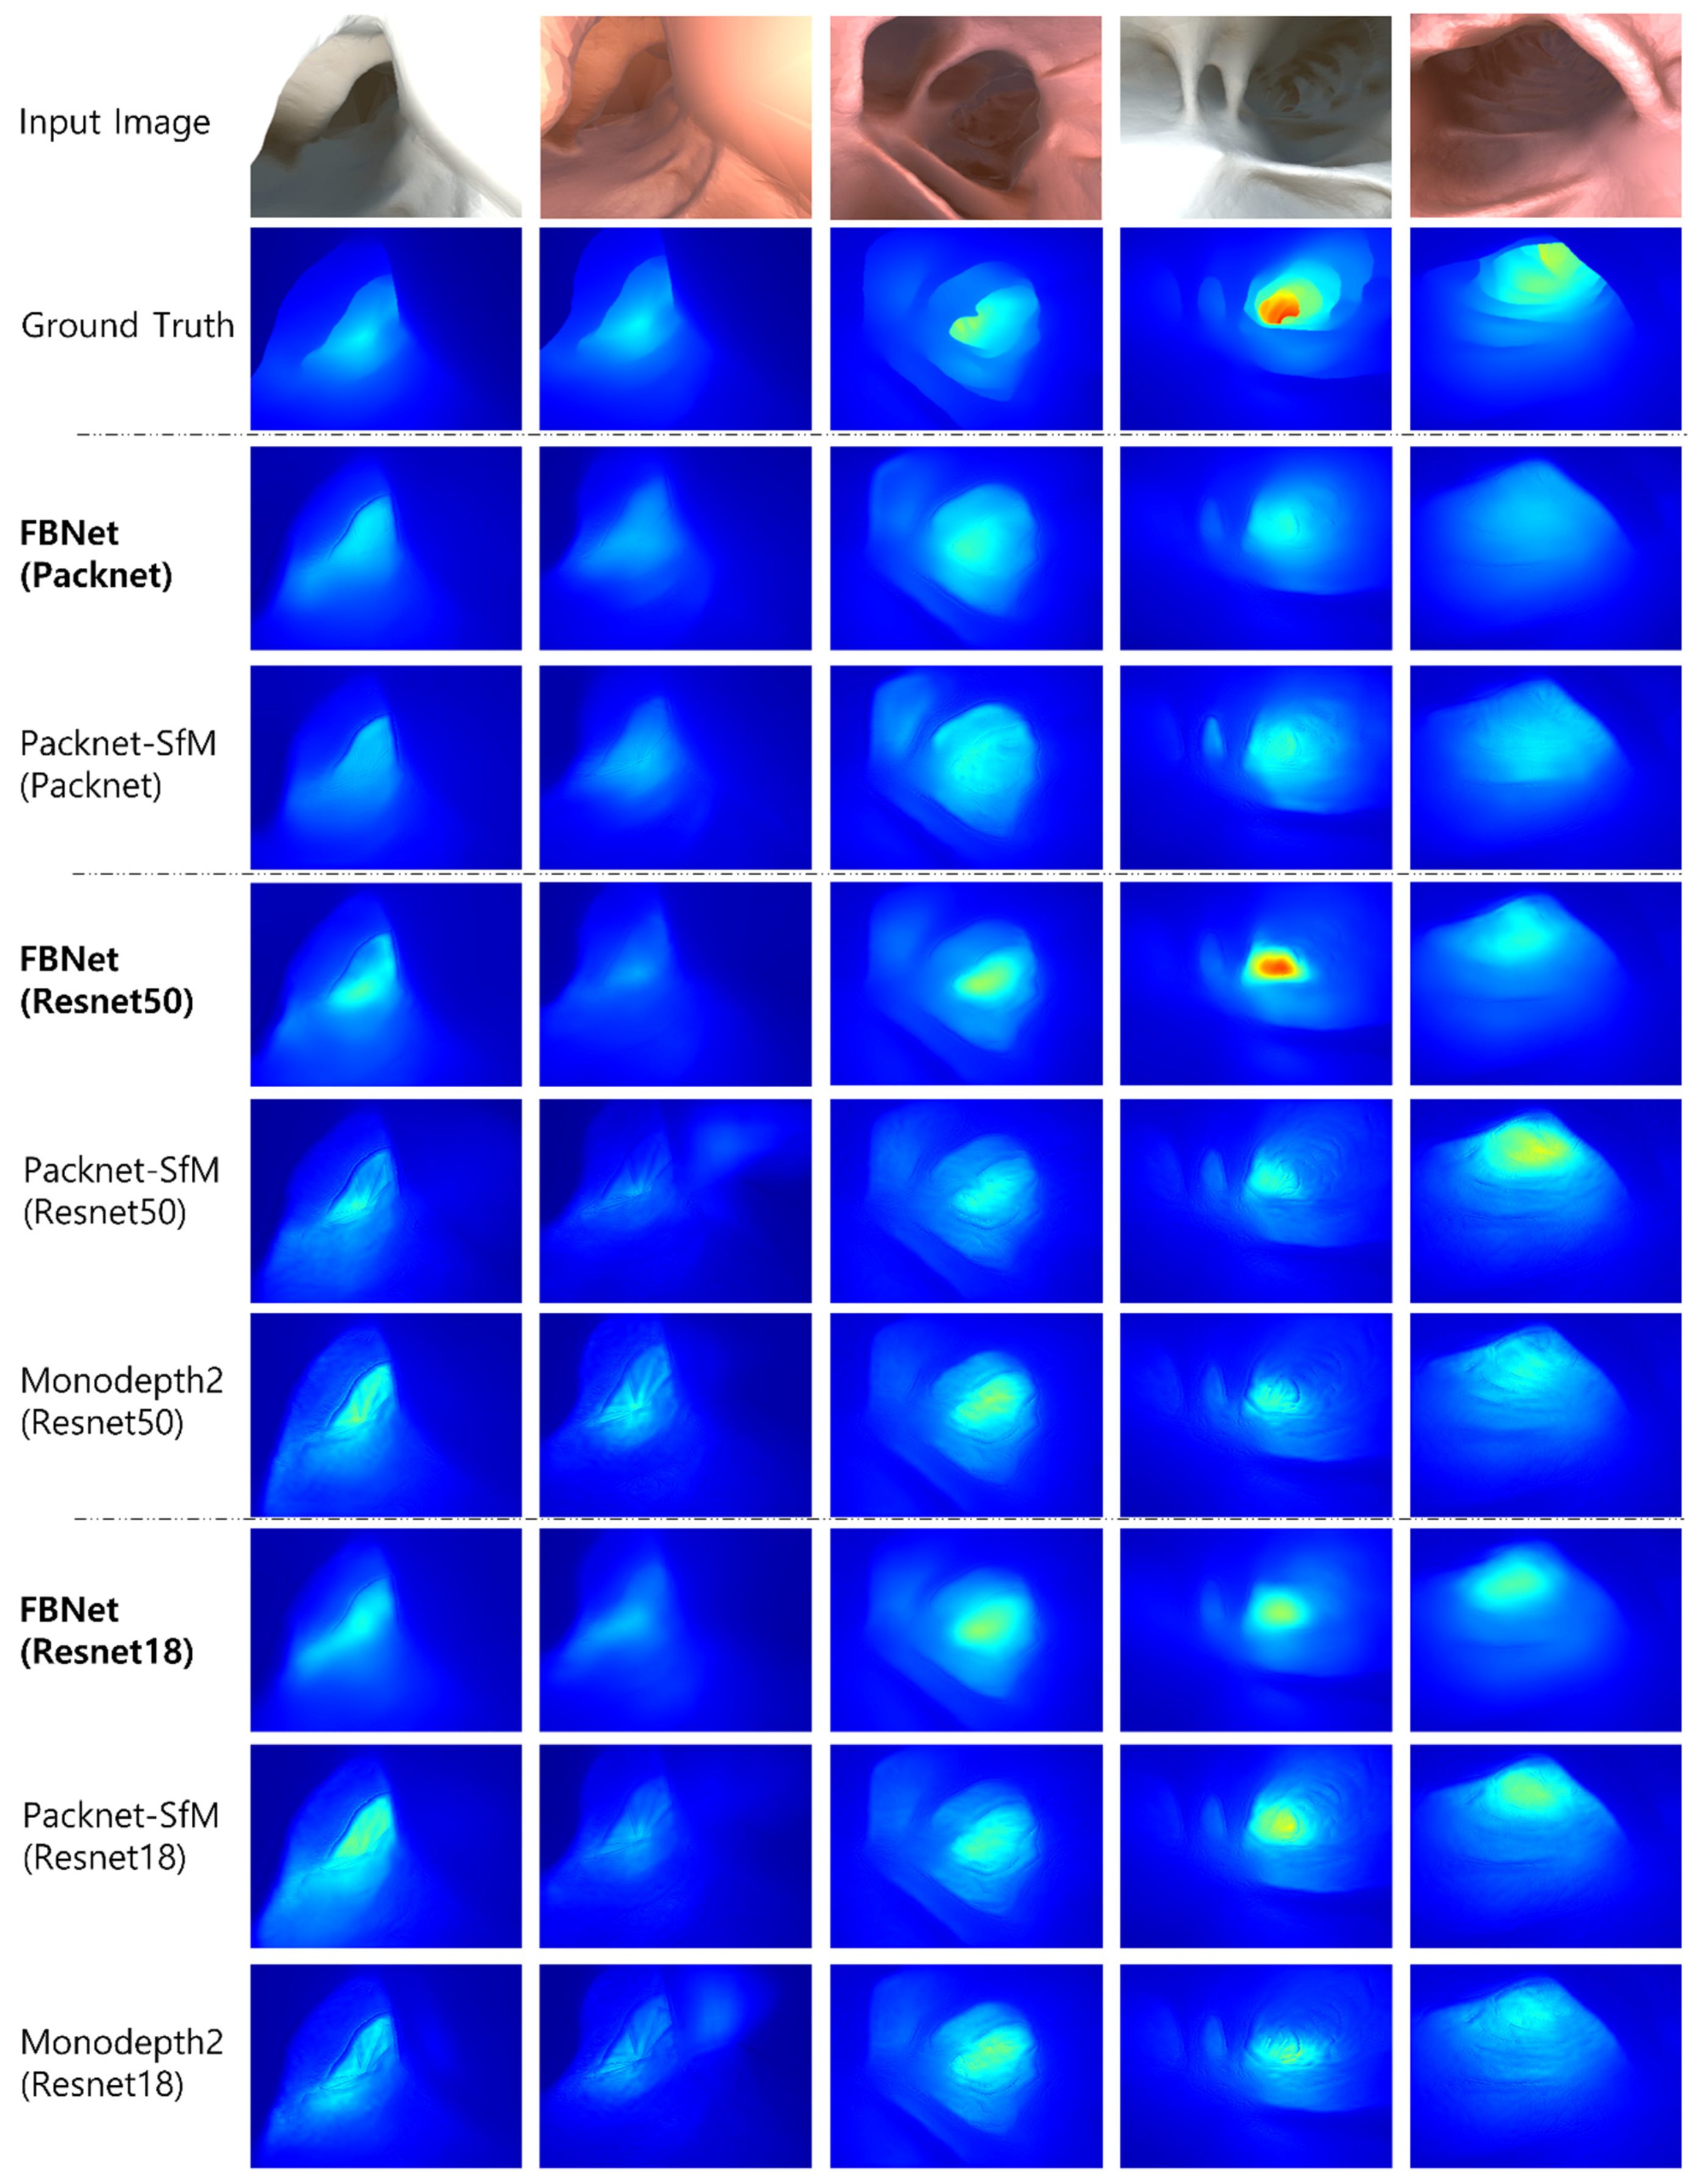

4.2. Comparison Study

4.3. Ablation Study